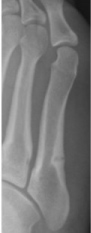

Patient 2: 20-year-male, basketball player

In February 2013, pain around the fifth metatarsal gradually worsened. The patient was diagnosed with a stress fracture of the fifth metatarsal (Figure 3a). However, bone union had not been achieved at 3 months after the original injury, so the patient was treated with one round of ESWT and fracture line became unclear at 4-weeks after the first round of treatment (Figure 3b). And he returned to basketball because of pain relief. However, he got pain around the fifth metatarsal again and refracture occurred at 3 months after ESWT (Figure 3c). The patient received surgery, screw fixation. However, bone union had not been achieved at 11-weeks after the refracture (Figure 3d). And then he was treated with two rounds of ESWT again over a period of 4-weeks and bone union was achieved at 9-weeks after the first round of re-ESWT (Figure 3e). He returned to competition at 12-weeks after ESWT.

Figure 3A: X-ray at 10 months after conservative therapy in Patient 2. View Figure 3A

Figure 3B: X-ray at 4 weeks after ESWT in Patient 2. View Figure 3B

Figure 3C: X-ray of refracture at 3 months after ESWT in Patient 2. View Figure 3C

Figure 3D: X-ray of non union at 11weeks after surgery in Patient 2. View Figure 3D

Figure 3E: X-ray of at 9 weeks after re-ESWT in Patient 2. View Figure 3E